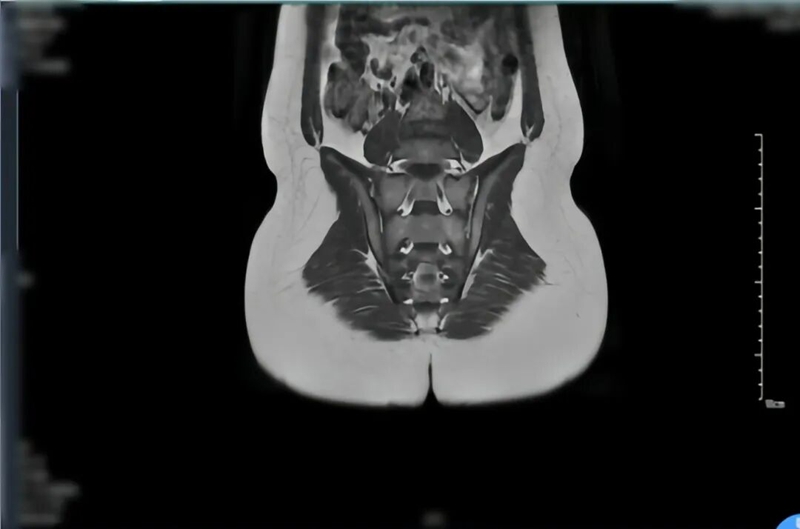

檢查結(jié)果顯示,小軒的血沉、C-反應(yīng)蛋白等炎癥指標(biāo)明顯升高,HLA-B27 篩查呈陽性(該指標(biāo)與脊柱關(guān)節(jié)病密切相關(guān),對診斷有重要參考價值);右足磁共振檢查發(fā)現(xiàn)距骨、跟骨存在“骨髓水腫”,骶髂關(guān)節(jié)影像也顯示關(guān)節(jié)面有骨髓水腫和炎癥跡象。

經(jīng)過一段時間的調(diào)理,小軒的狀態(tài)越來越好,近期復(fù)查關(guān)節(jié) MRI 顯示炎癥明顯改善,終于擺脫了疼痛的陰影,重新回到了綠茵場。